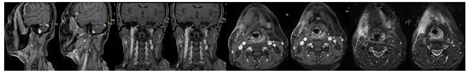

辅助检查:MRI提示右侧颌下软组织肿胀,渗出,邻近皮肤增厚,双侧颈部IB区多发小淋巴结,较大者为右侧,短径41 mm(图1)。病理提示颌下软组织非角化性未分化癌,免疫组织化学(Immunohistochemistry,IHC):P63(+),CK5/6(+), EGFR(+),S-100(个别细胞+),SOX10(-),P53(70%+), Ki-67(80%+)。EBV-EBER部分+。Epstein-Barr病毒(EB virus, EBV)脱氧核糖核酸(deoxyribonucleic acid, DNA) 7.58×103 copies/ml。